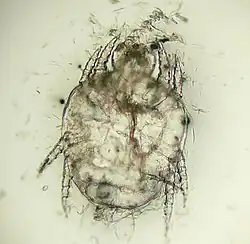

| Cheyletiella yasguri (?) from a dog | |

The adult mites are about 0.385 millimeters long, have eight legs with combs instead of claws, and have palpi that end in prominent hooks.[5] They do not burrow into the skin, but live in the keratin level. Their entire 21-day life cycle is on one host. They cannot survive off the host for more than 10 days.[6]

Diagnosis is by finding the mites or eggs microscopically in a skin scraping, combing, or on acetate tape applied to the skin.[8]